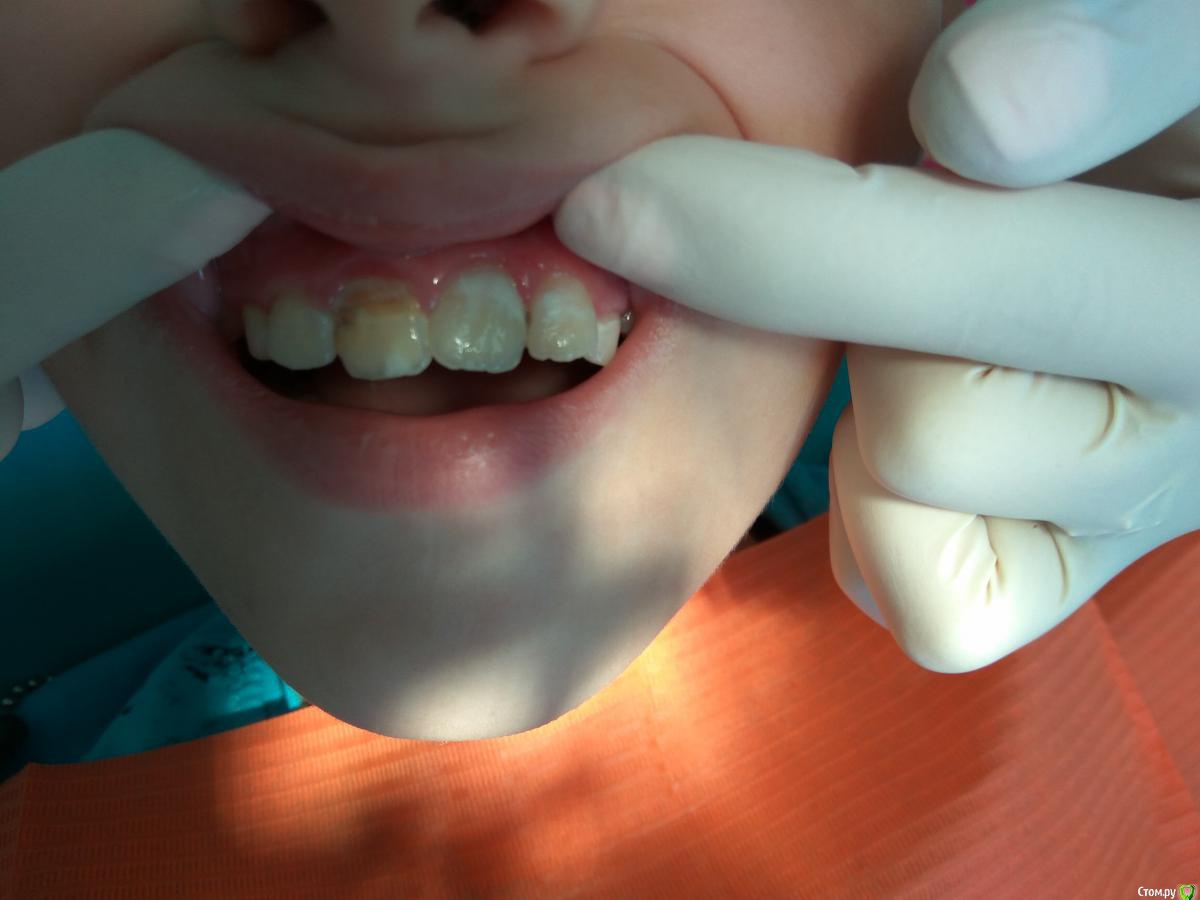

Тань Опубликовано 11 июня, 2018 Поделиться Опубликовано 11 июня, 2018 Сегодня пришёл парень 9,5лет с жалобами на подвижность коронки 11 зуба и боль при касании. В анамнезе в!!! апреле!!! упал с турника, была боль и небольшая подвижность. В клинике по месту жительства делали снимок, сказали динамически наблюдать, ничего не делали. Через некоторое время подвижность усилилась, пошли к знакомому ортопеду,он сказал что ничего кроме удаления, что ничего кроме съемного протезирования и в дальнейшем имплантации не сделать Пришёл к нам. Ортодонта нет, ортопеда нет, все выходные... Мне предстоит принять решение. Склоняюсь к удалению, но не решаюсь, знаю, что есть такая методика:оставить корень, чтобы не "ушла" кость. Хирург тоже не решился сразу удалять корень, пока удалил коронку, я провела эндо и временно каласепт под септопак оставила, вдруг можно сохранить хотя бы кость с корнем до имплантации. Жду ортодонта и ортопеда с выходных, а что вы, коллеги, на это скажете? Ссылка на комментарий

CRAZYDUCK Опубликовано 11 июня, 2018 Поделиться Опубликовано 11 июня, 2018 На последнем симпозиуме по травме - оставлять корень после эедодонтического лечения , с целью предупреждения атрофии альвеолярного отростка ВЧ. Ортодонт может выдвинуть немного корень , чтобы нарастить потом удобнее было . Можно попробовать коронковую часть прикрепить к корню.От родителей требуется серьезность в плане плановых осмотров . Что такое успех эндодонтии в данном случае ? Сколько простоит ? Сколько хватит сил организма - год ? Хорошо ! Два - тоже отлично . Лучше конечно до 21-22 лет ( индивидуально до созревания лицевого скелета). Родителям сразу сказать - корень будет удерживать кость - зуб все равно удалять . Эндо - как думаете делать , вопросы есть ? Ссылка на комментарий

Тань Опубликовано 11 июня, 2018 Поделиться Опубликовано 11 июня, 2018 На последнем симпозиуме по травме - оставлять корень после эедодонтического лечения , с целью предупреждения атрофии альвеолярного отростка ВЧ. Ортодонт может выдвинуть немного корень , чтобы нарастить потом удобнее было . Можно попробовать коронковую часть прикрепить к корню.От родителей требуется серьезность в плане плановых осмотров . Что такое успех эндодонтии в данном случае ? Сколько простоит ? Сколько хватит сил организма - год ? Хорошо ! Два - тоже отлично . Лучше конечно до 21-22 лет ( индивидуально до созревания лицевого скелета). Родителям сразу сказать - корень будет удерживать кость - зуб все равно удалять . Эндо - как думаете делать , вопросы есть ?Пока с гидроксидом кальция хочу повести, будет ли апексификация? Ссылка на комментарий

Дмитрий Л. Опубликовано 11 июня, 2018 Поделиться Опубликовано 11 июня, 2018 Всё верно. Если периодонтит пролечите, можно будет попробовать подтянуть корень и запротезировать. В дальнейшем. Ссылка на комментарий

CRAZYDUCK Опубликовано 11 июня, 2018 Поделиться Опубликовано 11 июня, 2018 Пока с гидроксидом кальция хочу повести, будет ли апексификация? время покажет . Лучше попробовать .Объяснить родителяи все возможные варианты ( осложнения и благоприятный исход), чтобы знали как действовать . Я лечила травму 1.1 спустя 8!!!!лет после травмы . Травма случилась в 8-9 летнем возрасте , спустя 8 лет - рубец от свищевогоизода и значительная резорбция корня , значительный очаг деструкции очаг костной ткани . Сейчас после года наблюдений все хорошо ( для этой ситуации) ребёнку сейчас 15 лет , а будущем планируем имплантацию после удаления ( стенки корня очень тонкие - не выдержат вкладку и коронку - треснут ) Ссылка на комментарий